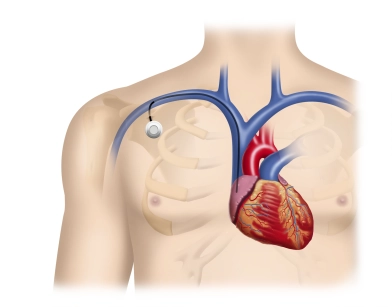

Aorta und Beckenstrombahn

Perkutane transluminale Angioplastie mit Stentimplantation bei Nierenarterienstenose bds.